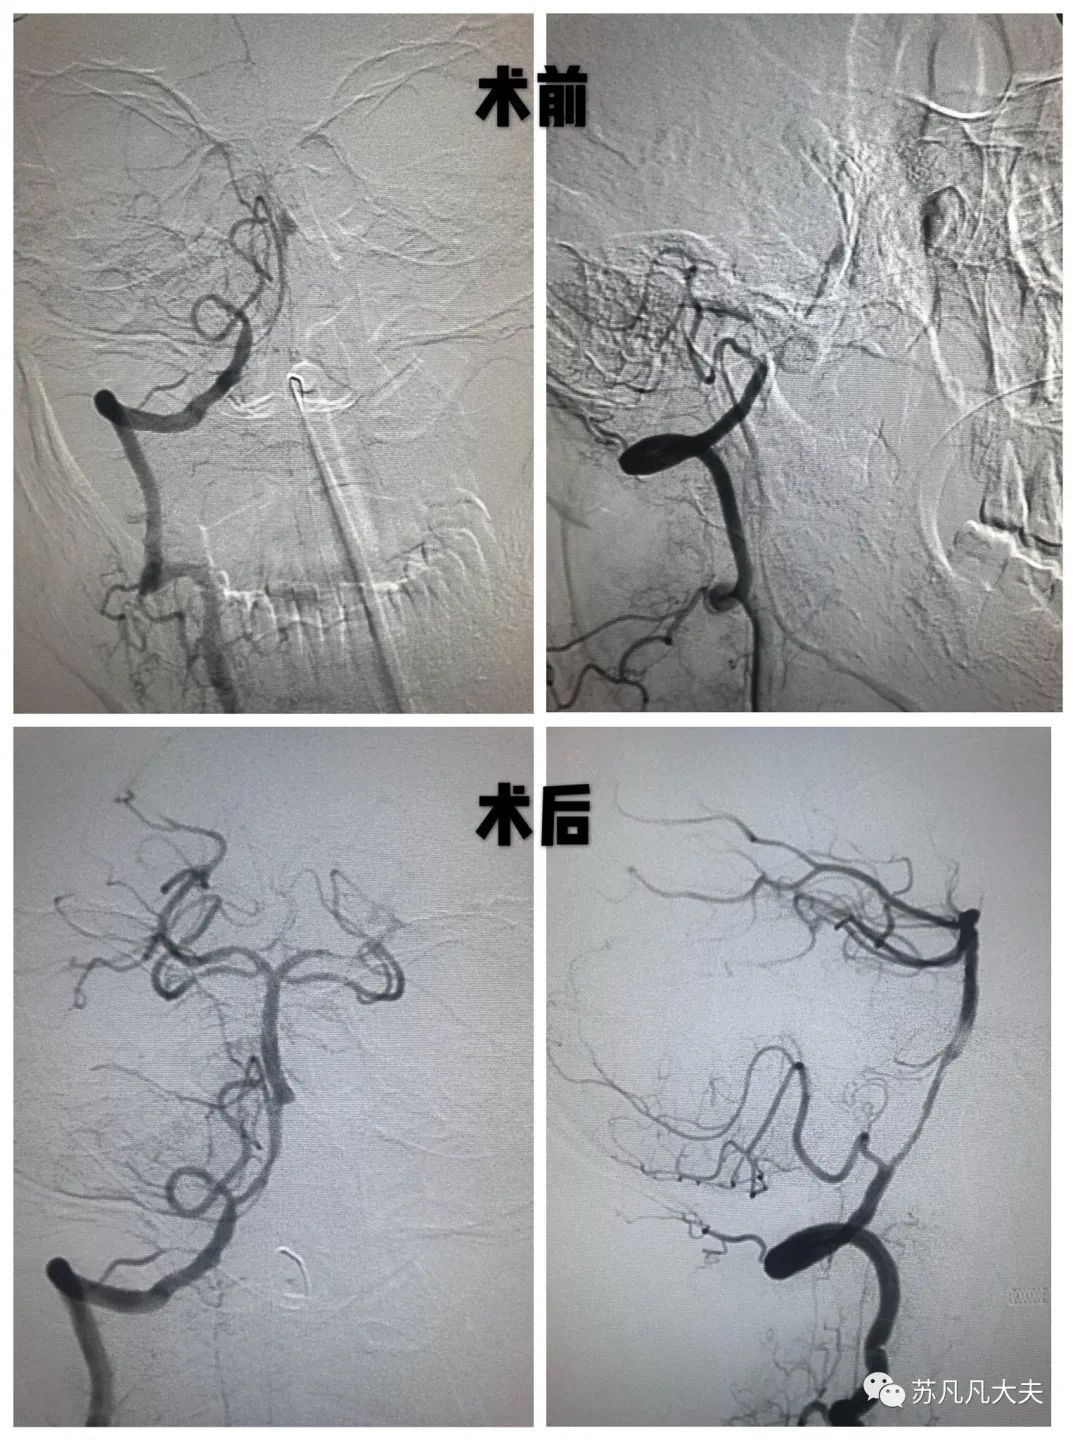

基底动脉闭塞

术前造影证实基底动脉主干闭塞,该病死亡率达90%

术前基底动脉闭塞